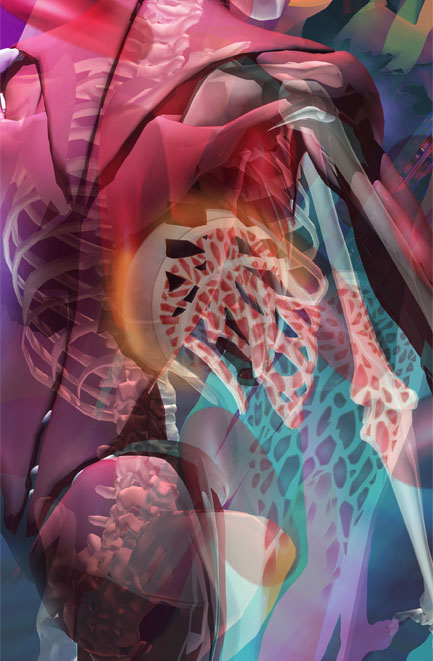

UP/DOWN

Installation of hanging fabric panels in the UCSD Biomedical Library

UP/DOWN

Interior graphics for UCSD Biomedical Library

Up/Down 2006

Detail focusing on muscle, bone and structure of the body from fabric panel installation for UCSD Biomedical Library.

Up/Down 2006

Detail focusing on circulating blood and it's parts from fabric panel installation for UCSD Biomedical Library.

Up/Down 2006

Detail focusing of fabric panel installation for the UCSD Biomedical Library.